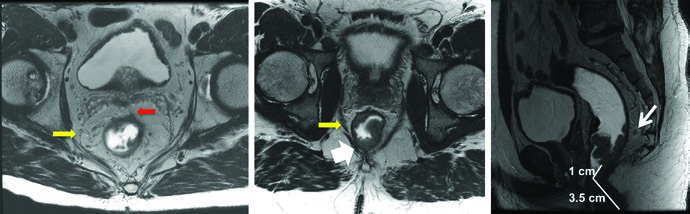

Endorectal ultrasound (EUS) evaluates invasion depth and nearby lymph node status, though it may under- or over-stage patients in approximately 20% of cases. MRI has become the standard imaging modality for preoperative staging — it detects mesorectal fat invasion (T3), involvement of adjacent structures (T4), assesses lymph node status, verifies the distance from the anal verge, and determines operability with negative margins.

PET/CT can help delineate gross disease, but areas of low radiotracer uptake should not supersede physical, endoscopic, or CT/MRI findings. In practice, PET/CT fusion with the planning CT is most useful for confirming GTV extent rather than replacing other imaging modalities.

The primary GTV (GTV-P) encompasses all gross disease identified on physical examination, endoscopy, and imaging. The nodal GTV (GTV-N) includes all visible perirectal, mesorectal, and involved iliac lymph nodes. In the absence of biopsy, any lymph node in doubt should be included as GTV. Low-lying rectal tumors require attention to the inguinal nodes, and tumors with anterior invasion into adjacent organs warrant evaluation of external iliac nodes.